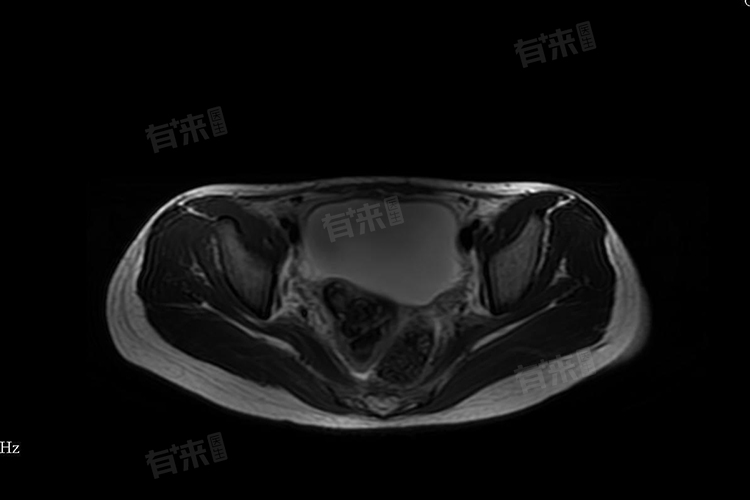

盆底积液指盆腔内积聚过量液体的病理状态,通常由炎症、外伤或其他疾病引发,主要症状表现为腰部酸痛、月经失调、白带增多。